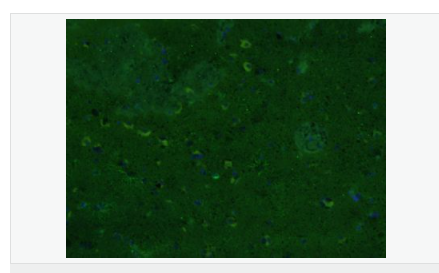

| 產品應用 | WB=1:500-2000 ELISA=1:5000-10000 IHC-P=1:200-1000 IHC-F=1:200-1000 Flow-Cyt=1μg/Test ICC=1:100 IF=1:200-800 (石蠟切片需做抗原修復) not yet tested in other applications. optimal dilutions/concentrations should be determined by the end user. |

| 產品介紹 | This gene encodes one of the major intermediate filament proteins of mature astrocytes. It is used as a marker to distinguish astrocytes from other glial cells during development. Mutations in this gene cause Alexander disease, a rare disorder of astrocytes in the central nervous system. Alternative splicing results in multiple transcript variants encoding distinct isoforms. [provided by RefSeq, Oct 2008] Function: GFAP, a class-III intermediate filament, is a cell-specific marker that, during the development of the central nervous system, distinguishes astrocytes from other glial cells. Subunit: Interacts with SYNM. Isoform 3 interacts with PSEN1 (via N-terminus). Subcellular Location: Cytoplasm. Note=Associated with intermediate filaments. Tissue Specificity: Expressed in cells lacking fibronectin. Post-translational modifications: Phosphorylated by PKN1. DISEASE: Defects in GFAP are a cause of Alexander disease (ALEXD) [MIM:203450]. Alexander disease is a rare disorder of the central nervous system. It is a progressive leukoencephalopathy whose hallmark is the widespread accumulation of Rosenthal fibers which are cytoplasmic inclusions in astrocytes. The most common form affects infants and young children, and is characterized by progressive failure of central myelination, usually leading to death usually within the first decade. Infants with Alexander disease develop a leukoencephalopathy with macrocephaly, seizures, and psychomotor retardation. Patients with juvenile or adult forms typically experience ataxia, bulbar signs and spasticity, and a more slowly progressive course. Similarity: Belongs to the intermediate filament family. SWISS: P14136 Gene ID: 2670 Database links: Entrez Gene: 2670 Human Entrez Gene: 14580 Mouse Omim: 137780 Human SwissProt: P14136 Human SwissProt: P03995 Mouse Important Note: This product as supplied is intended for research use only, not for use in human, therapeutic or diagnostic applications. 星形膠質細胞標志物 (Astrocyte Marker) GFAP是一個56kDa的中間絲蛋白(intermediate filament,IF),在中樞神經系統(tǒng)發(fā)育期是一個特異性的標志物,以區(qū)別星形細胞和其它膠質細胞。GFAP表達在皮層和海馬,急、慢性皮質酮治療時表達減少。 GFAP可以和人、大鼠、小鼠的GFAP反應,在正常和腫瘤性的星形膠質細胞陽性表達,而神經節(jié)細胞、神經元、成纖維細胞、少突膠質細胞和這些細胞來源的腫瘤細胞陰性表達,主要用于星形膠質瘤等中樞神經系統(tǒng)腫瘤的診斷和鑒別診斷,GFAP的缺乏可導致AD病。 |